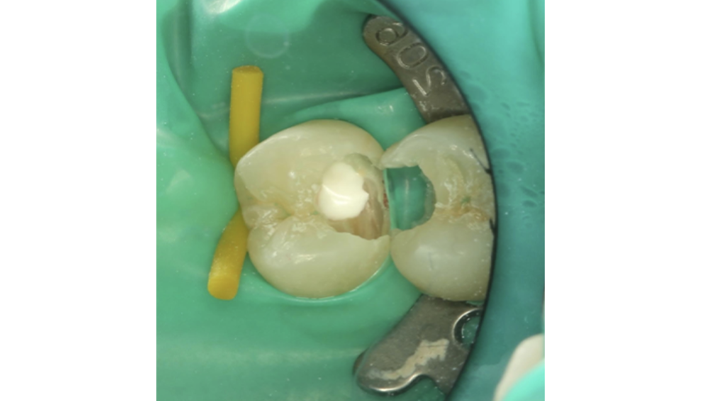

治療中

患者様は「他院で神経を取るしかないと言われたが、できれば神経を残したい」とのご希望で来院されました。初診時には冷たいものがしみる症状はありましたが、自発痛や打診痛はなく、診査の結果、歯髄を温存できる可能性があると判断しました。

治療では拡大視野下でむし歯の感染部分を正確に除去し、MTAを用いた歯髄温存療法を実施しました。

| 主訴 | 歯に穴が空いた |

|---|---|

| 治療期間 | 1ヶ月 |

| 治療費 | ¥33,000 |

| 治療内容 | むし歯が大きく、神経を残す治療(歯髄温存療法)を行い、神経を残しダイレクトボンディングにて修復しました。 |

| 治療のリスク | 治療後に痛みが出ることがあります。また、痛みが強くでる場合は神経を取る治療に移行することもあります。 |